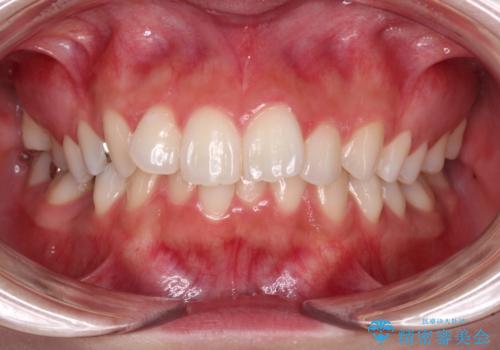

欠損した歯と前に飛び出した前歯 インプラント治療を併用したワイヤー矯正治療

- 上の前歯が下唇に当たる感覚と奥歯の欠損を気にして来院された患者様です。

上顎歯列全体を後方移動させたことで唇に当たる感覚は改善され、更には上下の正中位置も合わせることができました。